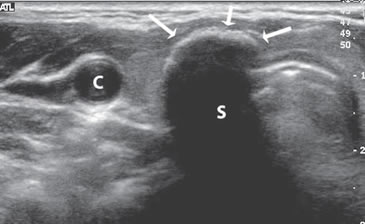

Un nódulo coloideo mixto puede aparecer como un quiste con un nódulo mural isoecogénico, excéntrico, que protruye hacia el lumen simulando una formación papilar, habitualmente vascularizado, que no corresponde a tejido neoplásico (Figura 19a). Si el componente sólido está rodeado por fluido, separado de la pared, y además tiene focos hiperecogénicos, es más difícil confundirlo con un tumor quístico (Figura 19b y c).

Figura 19. a) Nódulo coloideo, que muestra

una proyección de aspecto papilar hacia

el lumen, que corresponde a tejido no

neoplásico, igualmente vascularizado que

el resto del componente sólido del nódulo

(flecha abierta); b) y c) Nódulo coloideo,

predominantemente quístico, con componente

sólido (flecha), que muestra una forma

vegetante completamente rodeada de

coloide, con dos focos puntiformes en el

área más central.